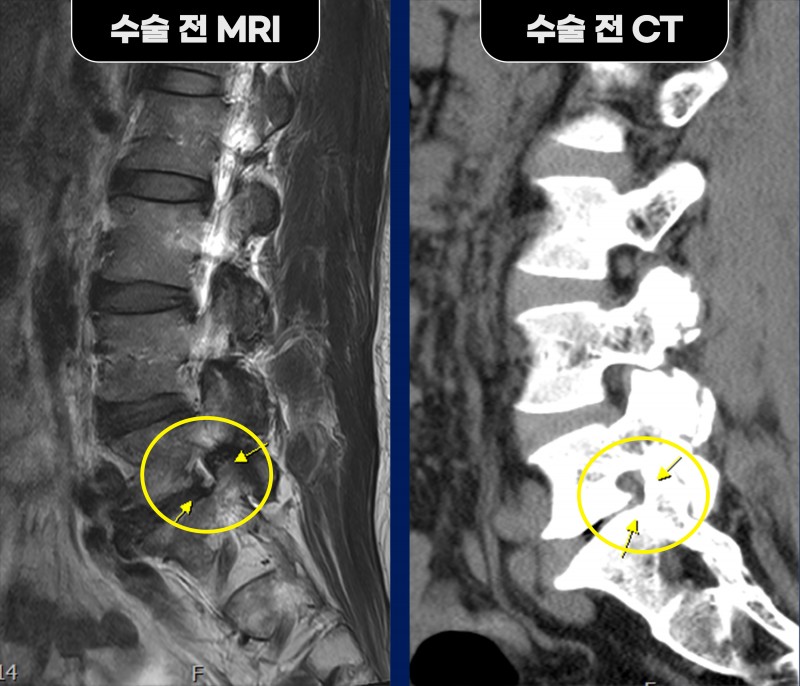

정밀 검사 결과, 단순 협착증이 아닌 요추 5번과 천추 1번이 부분적으로 붙어 가관절을 형성한

‘베르톨로티 증후군(Bertolotti syndrome)’으로 확인되었습니다.

이로 인해 요추 5번 신경이 추간공부터 추간공 외측까지 연속적으로 압박되고 있었습니다.